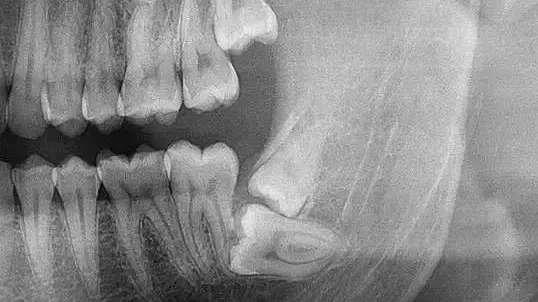

02、口腔全景片

确定是否长智齿

智齿埋在牙槽骨里

部分萌出或完全不萌出

生长方向:前、后、左、右?

拔智齿拍全景片

医生可观察到

牙齿长势、牙根位置和面部神经的距离